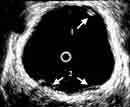

На Рис. 4 представлены эхограммы одного больного — трансабдоминальное и эндовезикальное исследование. Трансабдоминальное сканирование в данном случае не позволяет судить о глубине инвазии, а при эндовезикальном исследовании выявлена начинающаяся инвазия мышечного слоя, причем место инвазии визуализируется как гипоэхогенный участок на фоне гиперэхогенной мышечной ткани (стадия Т2а). Более четко визуализируется инвазия глубокого мышечного слоя (стадия Т2в) (Рис. 5).

Рис. 4. Рак мочевого пузыря стадия Т2а (стрелкой указана начинающаяся инвазия мышечного слоя).

(Слева) Трансабдоминальное сканирование.

(Справа) Эндовезикальное сканирование.